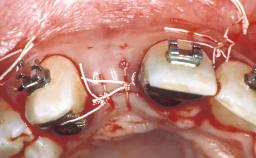

Replacement of an Upper Right Central Incisor with a Regular Neck Implant, Restored with an All-Ceramic Crown, Cemented

A healthy 32-year-old female patient presented for a consultation on treatment options to restore her missing central incisor 11. She reported of a recent sporting accident in which she had lost part of her tooth. The remaining tooth structure and root had been removed by a local periodontist, followed by a socket-preservation procedure. She was unaware of current treatment options to replace her missing tooth and wanted to explore the most esthetic and functional options available. A brief consultation showed that the patient was not interested in orthognathic procedures to address her maxillary overbite, nor in any alternative procedures to lower her high lip line. With her interim prosthesis in place, an evaluation of her smile highlighted several malpositioned teeth surrounding tooth 11. Comparing the maxillary canines, it was evident that tooth 13 was rotated. Comparison of the lateral incisors revealed that tooth 12 had a flared appearance.